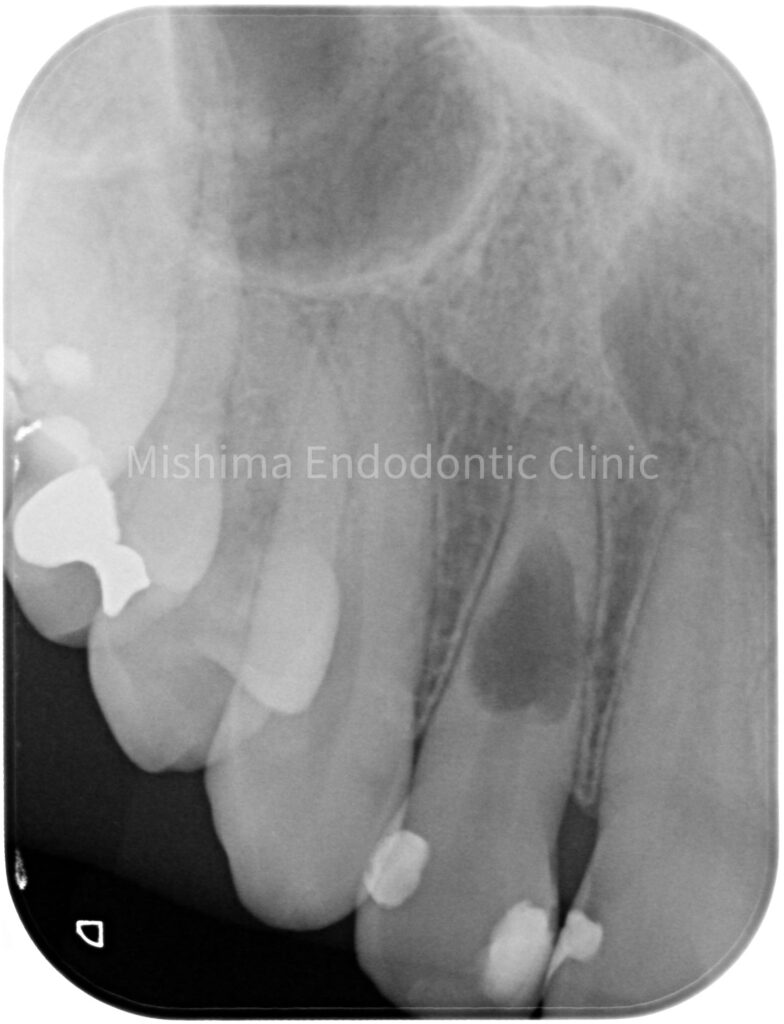

Before

| 治療内容 | 歯髄診査により生活反応は認めない。X線にて内部炎症性吸収と診断。根管内を精査したところ、吸収部より根尖の歯髄は生活していた。根管治療を行い、バイオセラミックのパテにて充填。術後、症状、以上所見は認めず経過は良好。 |

術前